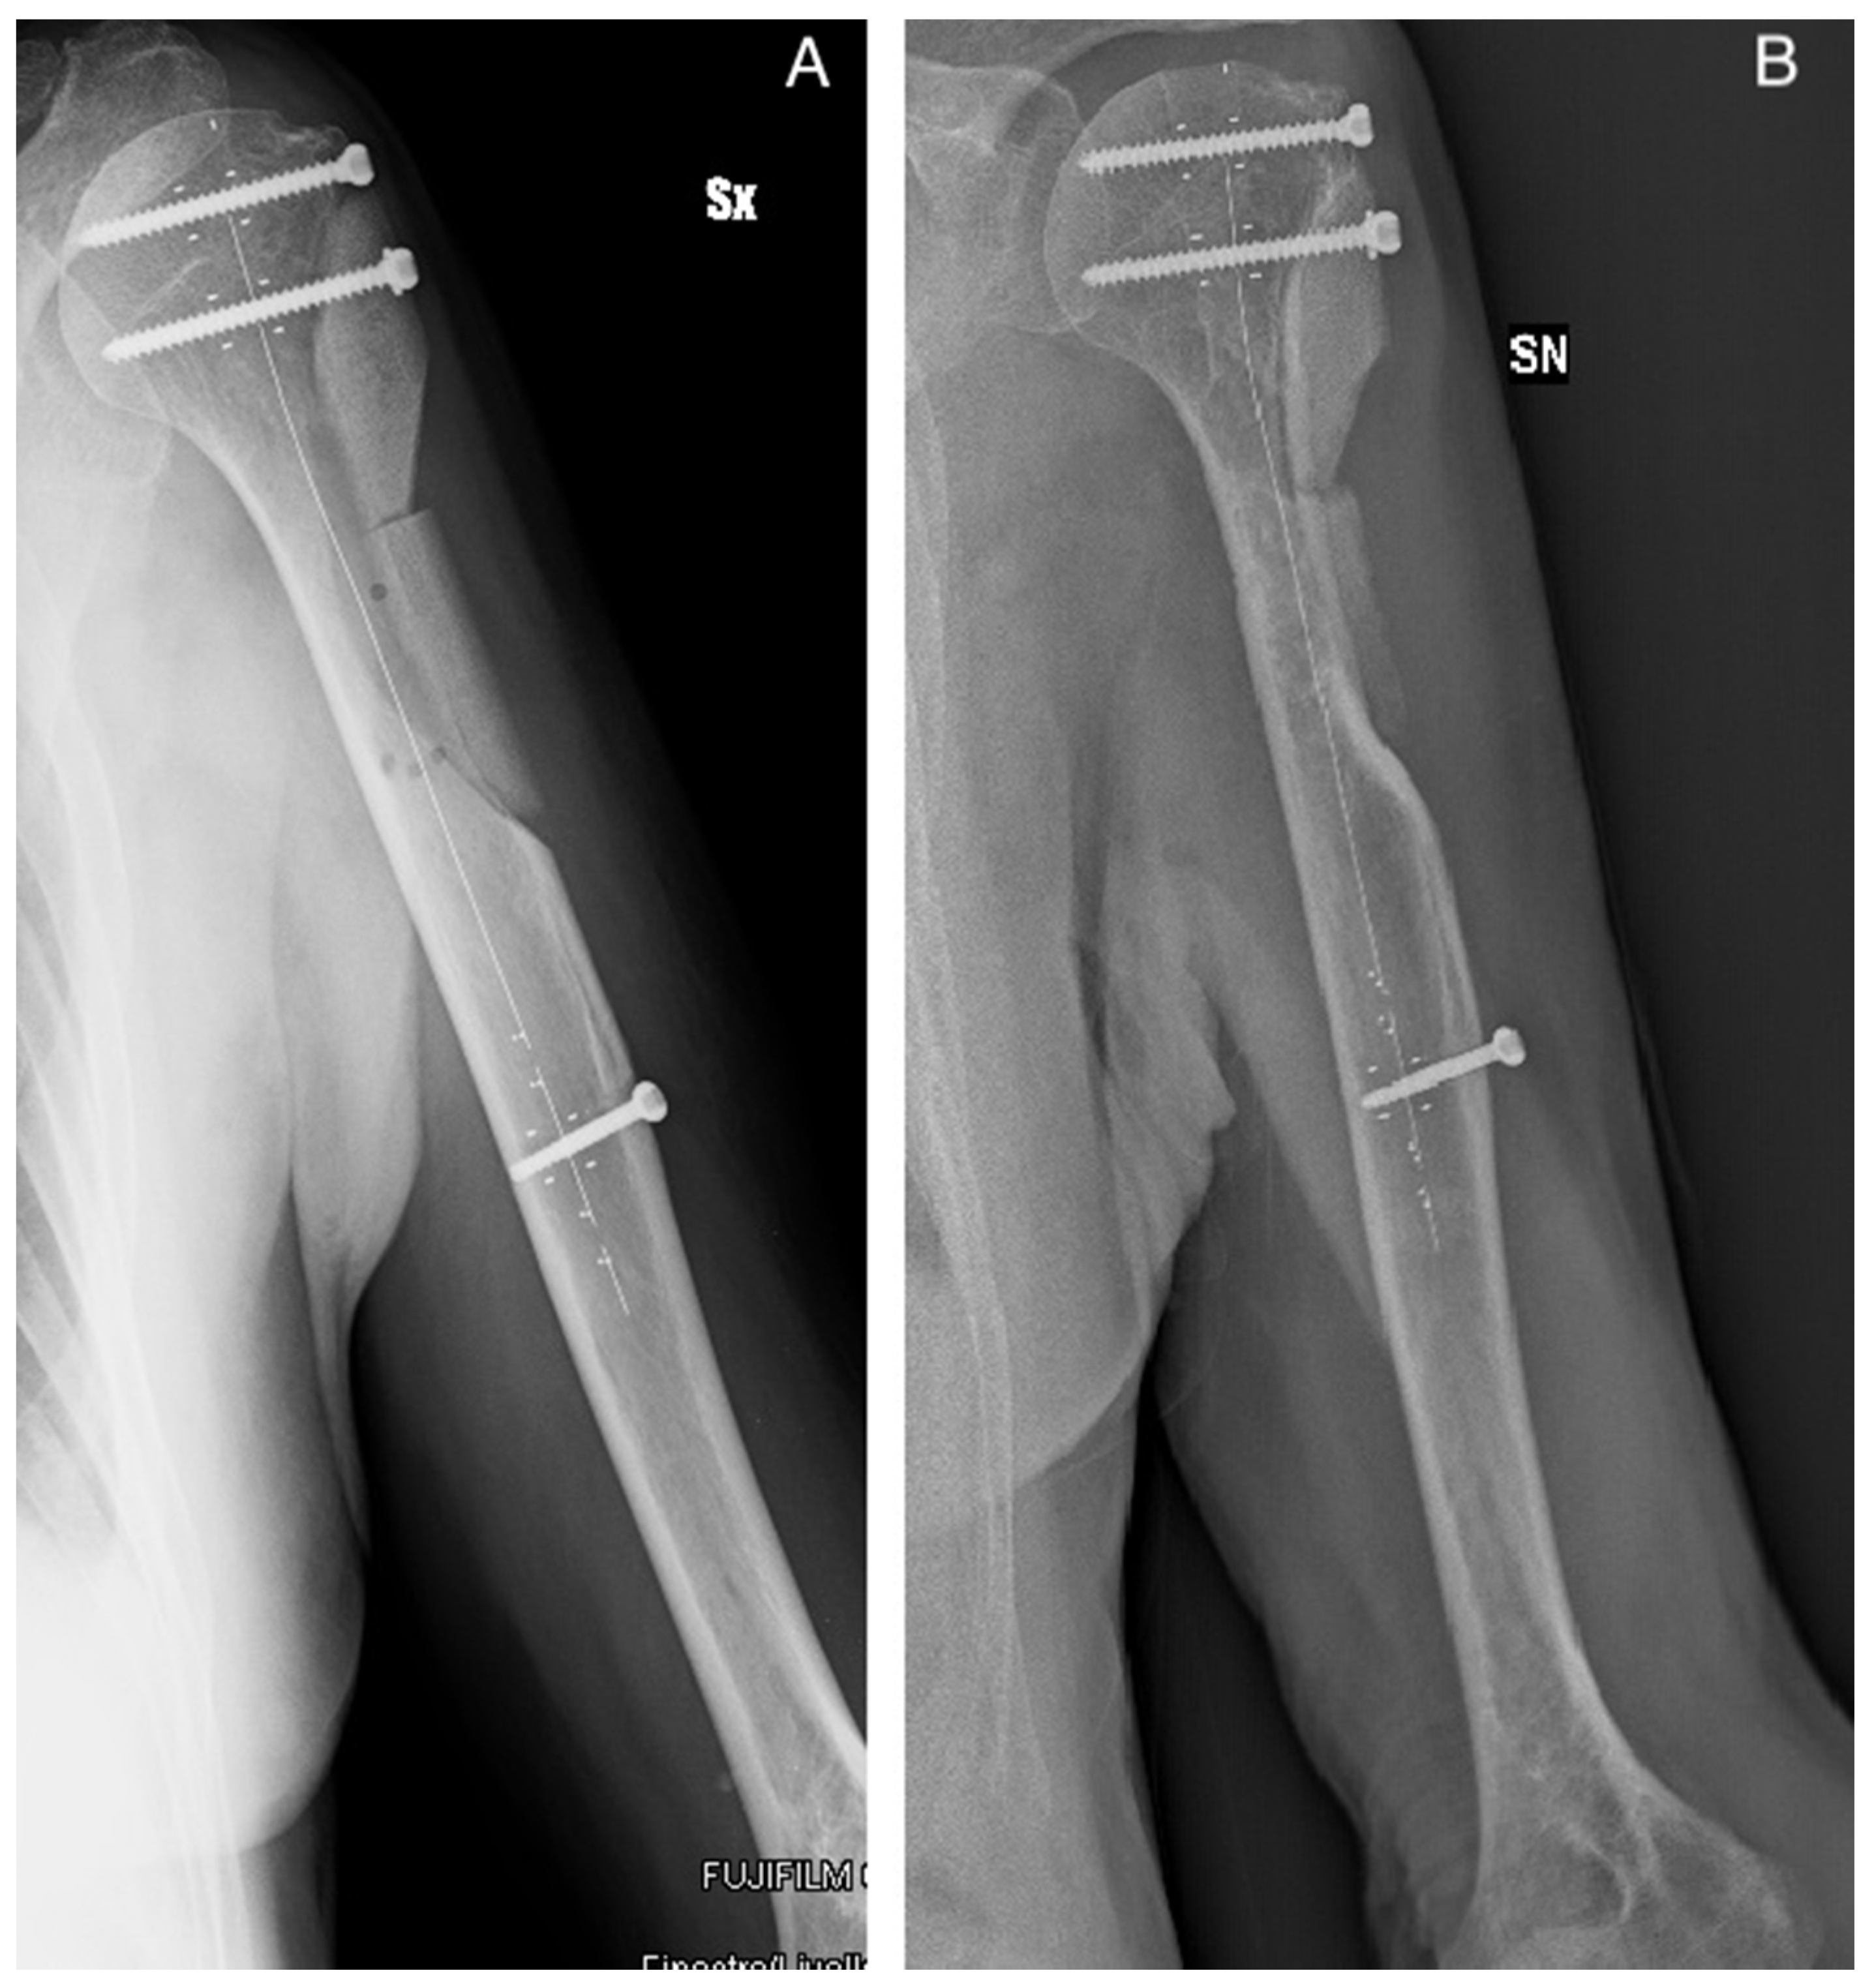

The handling and workability of this biomaterial and its mechanical properties were known, as they were previously investigated in vitro [20,37] and assessed in clinical applications [19,36,37]. Moreover, complex cases were also investigated in silico [38] in order to determine biomaterial limits under extreme loads. These evidences, together with the analysis of each case here reported (see Table 2), allowed for early weight-bearing and avoiding a preventive bone fixation in most of the patients. Only in four cases was bone stabilization necessary because for three of them more than two thirds of the cortical circumference of the tibia or femur were involved, in patients with a relevant Body Mass Index. In the other case, an extensive cortical resection was performed. In some specific cases, the positioning of SB blocks longitudinally along the major mechanical axis of the bone may give the opportunity to obtain higher stability [38]. The radiological evaluation of the graft integration was good or excellent according to Mosetto’s six-grade score in 95% of the sample (20 out of 21 patients). Figure 2 shows the progressive optimal integration of SB after curettage of a proximal femur Fibrous Dysplasia. The poor result was in the patient with myxofibrosarcoma, where the SB blocks were used to reconstruct the lateral cortex of the humerus. In this case, the radiolucent line surrounded the whole graft, which was also partially reabsorbed (Figure 3). At the same time, no major complications occurred. The risk for recurrence is related to the characteristics of the disease and the performed curettage. A more aggressive curettage, if indicated, can also increase local bleeding and help bone healing and graft integration. This product appeared valid and safe not only in benign bone diseases. The case of recurrence occurring to the patient with patellar GCT initially presented an interruption of the anterior patellar cortex and an involvement of the surrounding soft tissues. An inadequate lesion removal may have caused an early relapse and progression of the disease, but as seen on the MR scan and intraoperatively, an important disease dissemination occurred in the host tissue. On the contrary, the SB block previously implanted was still intact and was not invaded by pathological tissue. Such preliminary results may suggest that SB does not help vehiculate the disease.

Figure 3. Patient 18. Radiological control after one month from Myxofibrosarcoma excision with (A) lateral proximal humerus cortical resection and reconstruction with two SB blocks. (B) The radiograph on the right shows a line of radiolucency and a partial resorption of the lowest block due to the incomplete coverage of the graft and its isolation from the soft tissues. Abbreviations: SX and SN stand for Left.